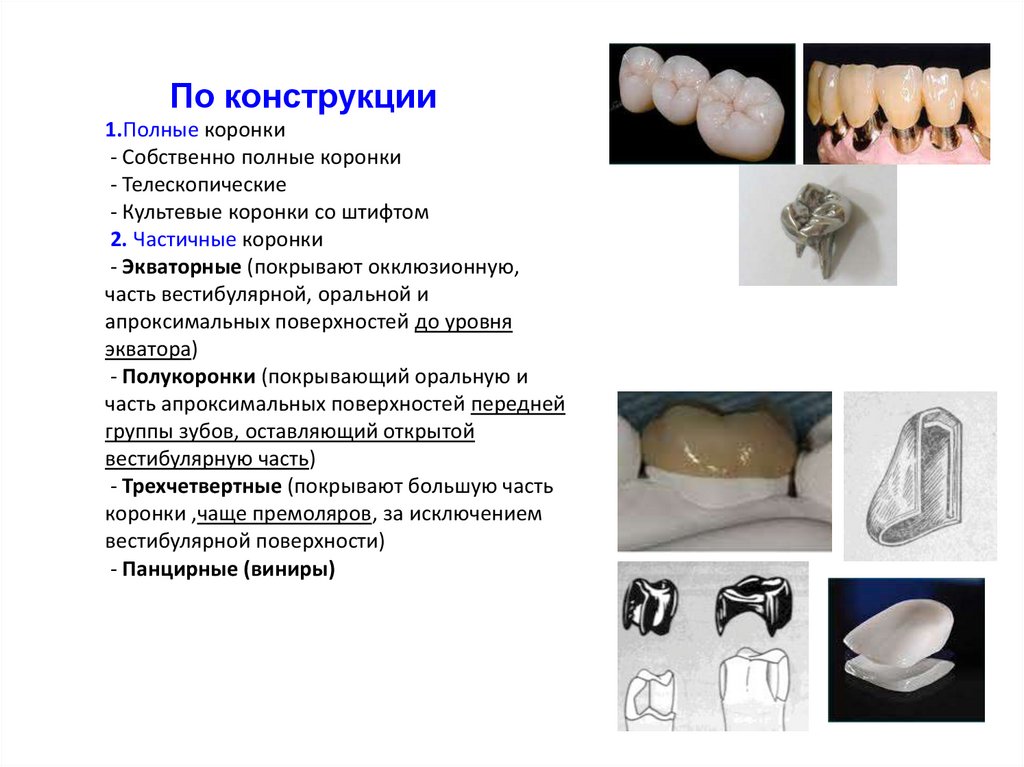

Разновидности зубных коронок и их особенности